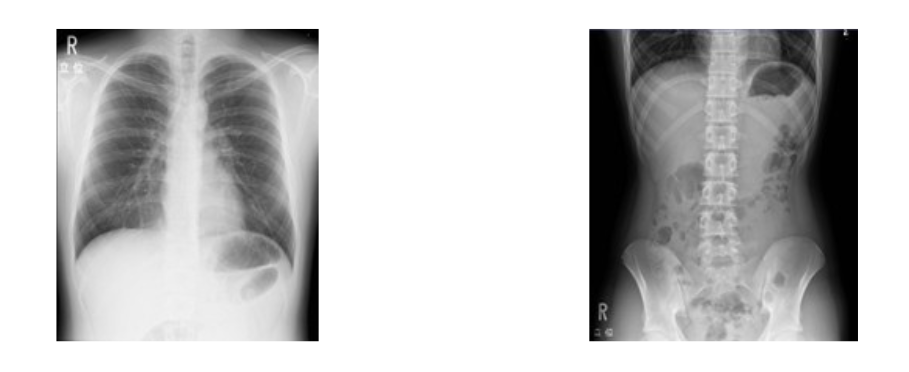

【胸部】 【腹部】

胸部撮影では、肺に異常な影があるかどうか、心臓の形に異常があるかどうかを調べます。

腹部撮影では、炎症や石灰化、腸管内のガスや食物残渣の有無、尿路結石や腹水などの疾患を調べます。